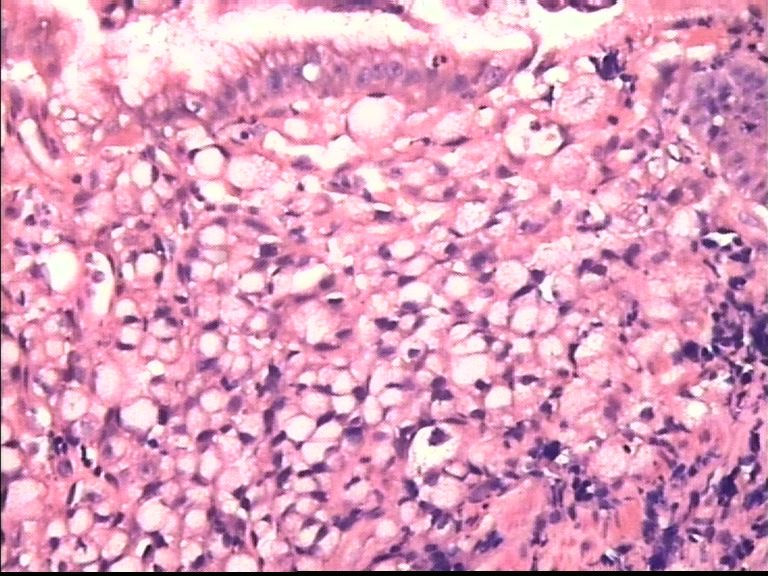

胃部溃疡3cm 53岁 男

仅此局部形态,应该是印戒细胞癌,最好有更多的背景资料

印戒细胞癌

倾向印戒细胞癌

诊断印戒细胞癌

印戒细胞癌高度可疑,建议做:CK、CD68、PAS帮助诊断。